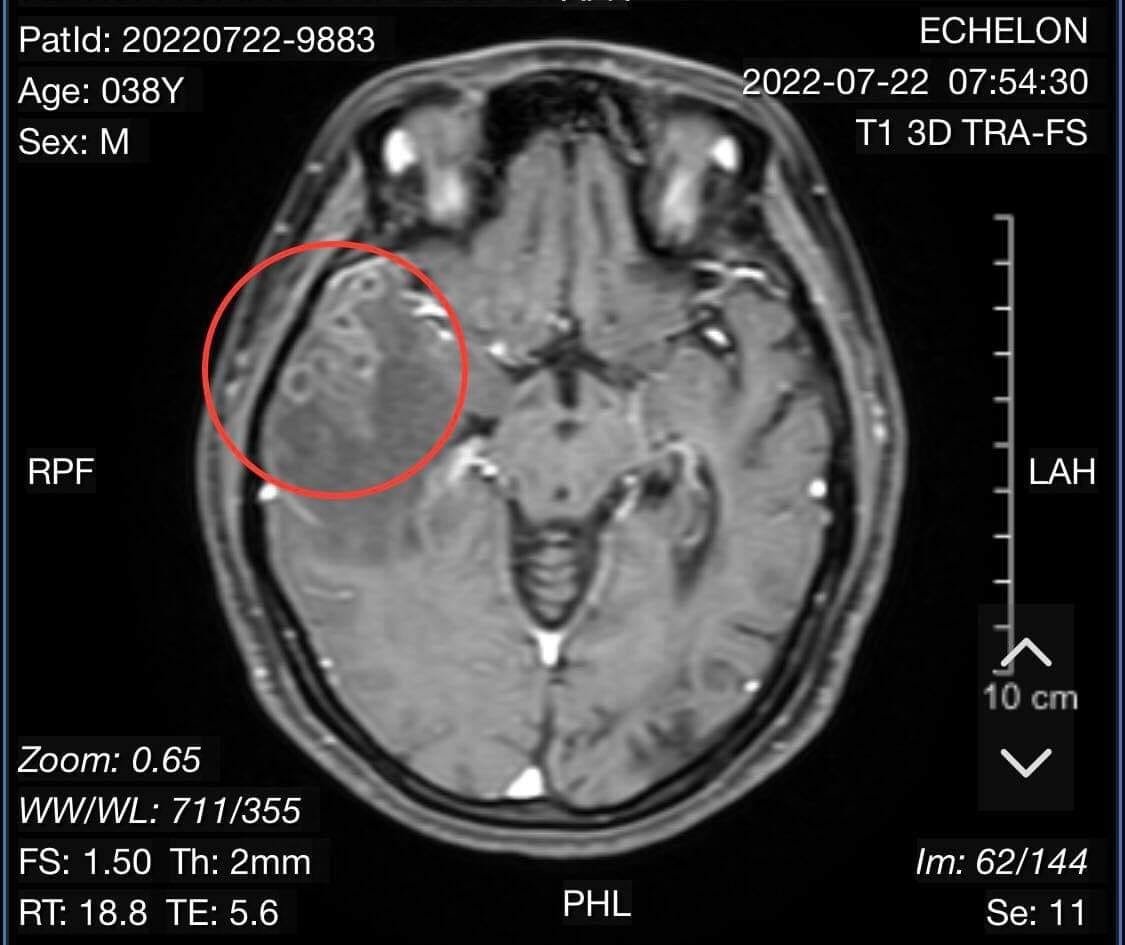

Bệnh nhân được các bác sĩ chuyên khoa Ngoại Thần kinh cho các chỉ định cận lâm sàng. Qua hình ảnh chụp cộng hưởng từ sọ não có tiêm chất tương phản, cho thấy người bệnh bị tổn thương não do sán. Kết quả xét nghiệm giải phẫu bệnh là mô não có ổ viêm hạt, trung tâm chất hoại tử, đại bào nhiều nhân, tương bào và tế bào sợi. Kết luận tổn thương viêm não do nang sán.

Kết quả chụp cổng hưởng từ sọ não cho thấy có nang sán trong não người bệnh. Ảnh: BVCC.